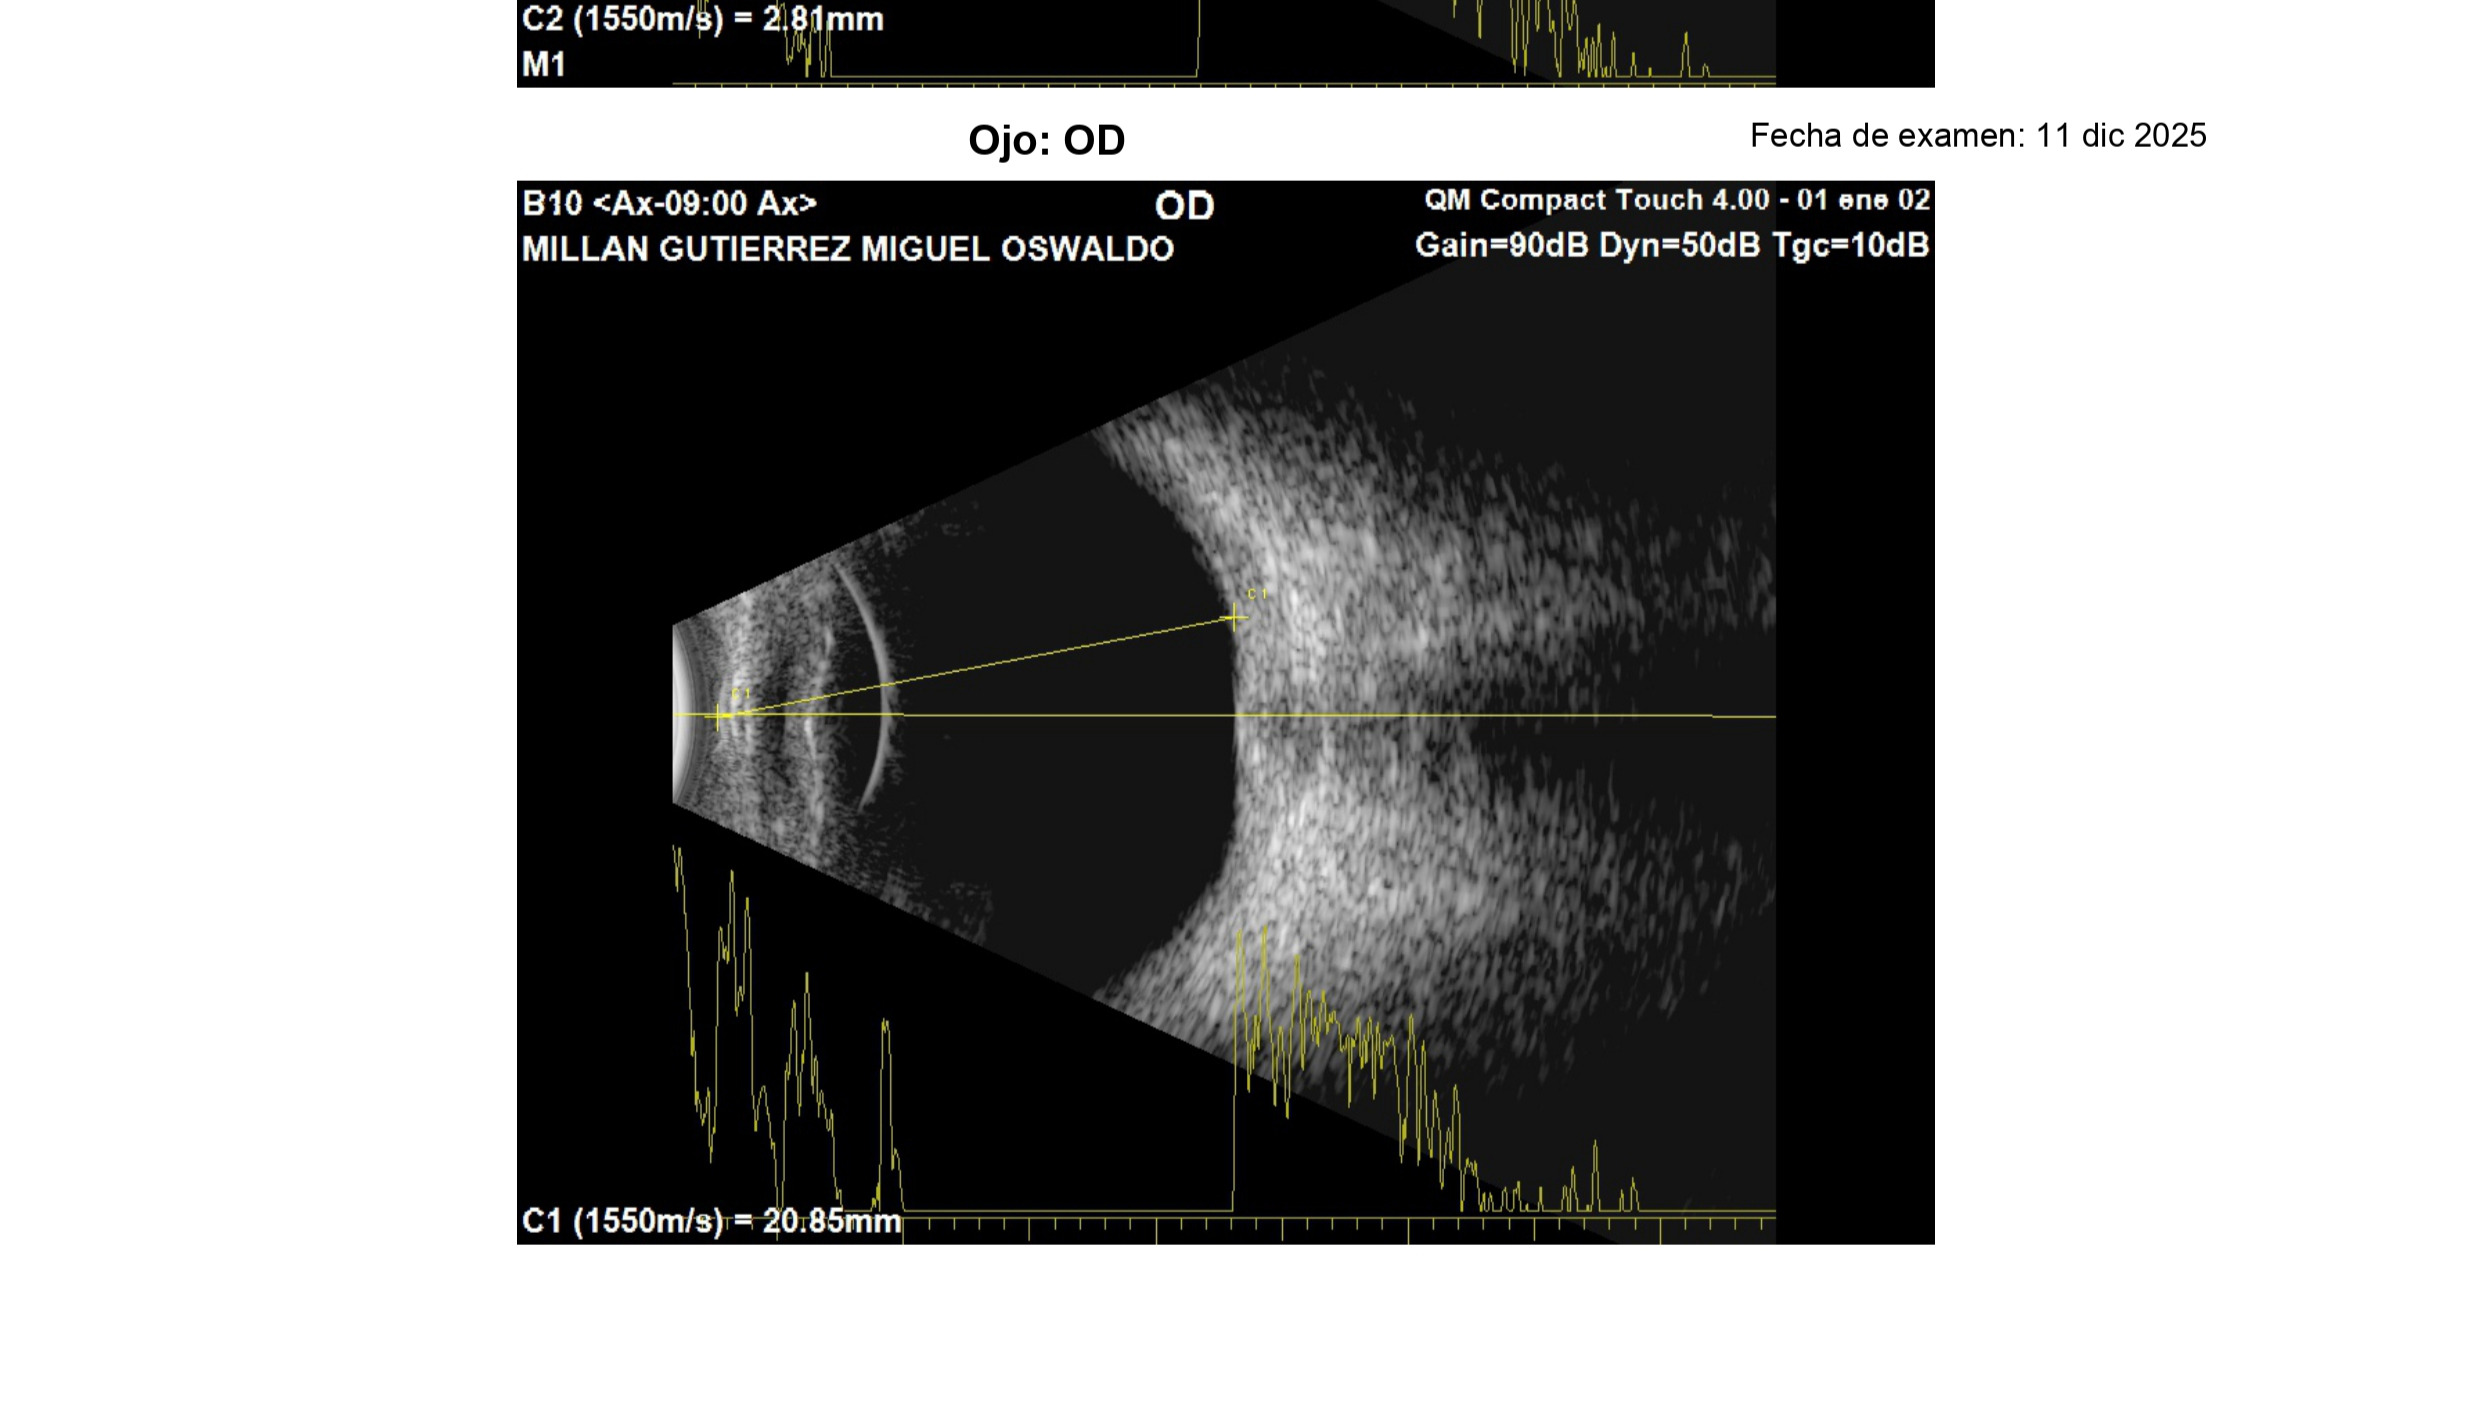

El 11 de diciembre fui diagnosticado con melanoma coroideo, un tipo de cáncer ocular poco común que crece debajo de la retina. En mi caso, el tumor ya provocó un desprendimiento de retina y, si no se trata a tiempo, puede extenderse a órganos como el hígado o los pulmones.

On December 11th, I was diagnosed with choroidal melanoma, a rare type of eye cancer that grows beneath the retina. In my case, the tumor has already caused a retinal detachment and, if not treated in time, it can spread to organs such as my liver or lungs.